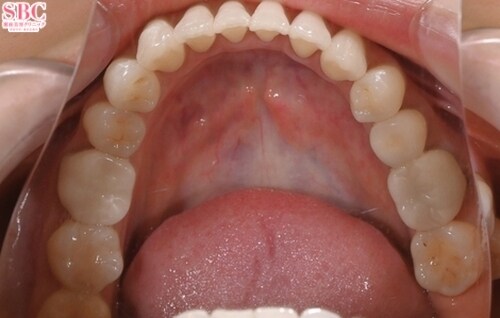

施術後8ヶ月後

「前歯の捻じれ、歯の重なりがきになる」とのことでインビザラインモデレートにて治療したお写真になります★約7か月ほどできれいに並びました!マウスピース矯正は一日20時間以上マウスピースを使用し1週間?10日位の交換で進めていきます。スペースが足りない場合はIPR(歯と歯の間を削ってスペースを作る処置)やゴムかけが必要になる場合がございます。どのプランが適切かカウンセリング時にご説明させていただきます★ご興味ある方は是非カウンセリングにいらしてくださいませ。お待ちしております!

「前歯の捻じれ、歯の重なりがきになる」とのことでインビザラインモデレートにて治療したお写真になります★

約7か月ほどできれいに並びました!

マウスピース矯正は一日20時間以上マウスピースを使用し1週間?10日位の交換で進めていきます。

スペースが足りない場合はIPR(歯と歯の間を削ってスペースを作る処置)やゴムかけが必要になる場合がございます。

どのプランが適切かカウンセリング時にご説明させていただきます★